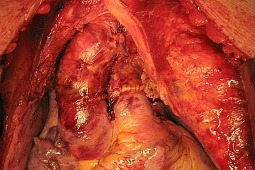

Nowatorska operacja w Polsce: lekarze Centrum Zdrowia Dziecka, przy współpracy specjalistów z Instytutu Kardiologii w Warszawie – Aninie z powodzeniem przeszczepili serce czternastoletniemu chłopcu.

-Operacja zakończyła się powodzeniem, przeszczepienie powiodło się – powiedział termedii.pl prof. Bohdan Maruszewski, kierownik Kliniki Kardiochirurgii Instytutu Pomnika Centrum Zdrowia Dziecka.

Biorcą był Jakub, czternastoletni chłopiec, który przez wiele miesięcy pozostawał podłączony do aparatury wspomagającej pracę serca. –Operacji dokonaliśmy przy współpracy ze specjalistami z z Instytutu Kardiologii w Warszawie – Aninie – informuje Joanna Komołka, rzecznik Centrum Zdrowia Dziecka.